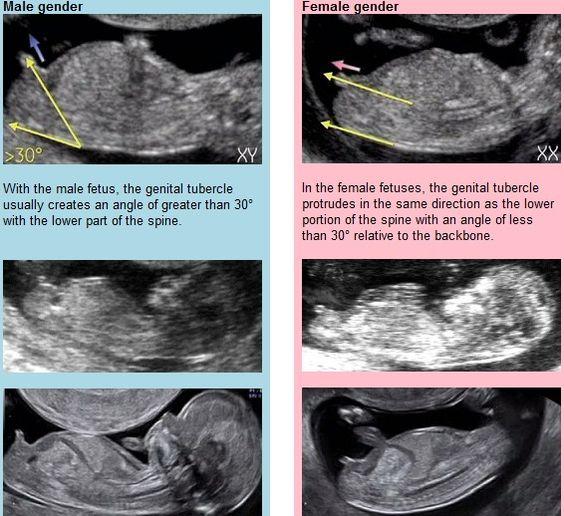

@mzacikova děkuji za odpověď a mohu se zeptat podle čeho se to dá poznat ?😊